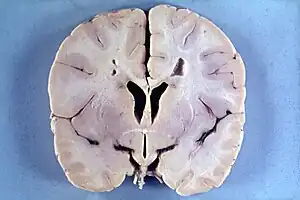

| Brain of a 4-year-old boy with Alexander disease showing macroencephaly and periventricular leukomalacia (note brownish discoloration around the cerebral ventricles) | |

Delays in development of some physical, psychological and behavioral skills; progressive enlargement of the head (macrocephaly), seizures, spasticity, and in some cases also hydrocephalus, idiopathic intracranial hypertension, and dementia.[2]

Alexander disease belongs to leukodystrophies, a group of diseases that affect the growth or development of the myelin sheath. The destruction of white matter in the brain is accompanied by the formation of fibrous, eosinophilic deposits known as Rosenthal fibers.[2][6][7] Rosenthal fibers appear not to be present in healthy people,[6][8] but occur in specific diseases, like some forms of cancer, Alzheimer’s, Parkinson’s, Huntington’s, and ALS.[6][8][9] The Rosenthal fibers found in Alexander disease do not share the distribution or concentration of other diseases and disorders.[6]

Alexander disease causes the gradual loss of bodily functions and the ability to talk. It also causes an overload of long-chain fatty acids in the brain, which destroy the myelin sheath. The cause of Alexander disease is a mutation in the gene encoding GFAP.[2][6][3][4][10][9]